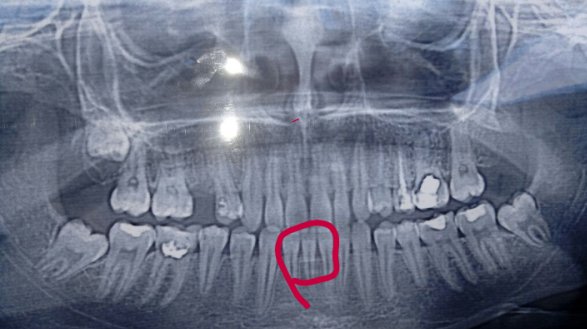

• Да, безусловно, выпрямить нижний зубной ряд можно. Вам необходимо сделать снимок, который называется ортопантомограмма и обратиться к стоматологу -ортодонту. В очень редких случаях проводится лечение на одной челюсти, как правило, лечение проводится на обеих челюстях для создания идеальных контактов между зубами. Сумма лечения может варьироваться в зависимости от компании п читать далее

• Необходим осмотр и панорамный рентгеновский снимок зубов, оценка прикуса и соотношения зубов. В первую очередь следует лечить центральные резцы так как, по фото, они поражены кариесом. После проконсультируйтесь очно со стоматологом-ортодонтом для составления плана лечения. Скорее всего, в вашем возрасте чаще всего ставят пластины, а брекеты после 14 лет, когда полностью сфор читать далее

• Необходим осмотр и панорамный рентгеновский снимок зубов. Удалять здоровые зубы не нужно. У Вас, по фото, скученность зубов из-за нехватки места в зубном ряду и недоразвитие челюстных костей. Следовательно, и неправильный патологический прикус. В таком случае, требуется лечение брекет-системой. Проконсультируйтесь очно со стоматологом-ортодонтом для составления плана лечения.

• Восьмые зубы ("зубы мудрости") могут в Вашем случае повлиять на положение зубов. Они немного наклонены в сторону седьмых зубов. Но судя по данному снимку, между другими зубами имеются промежутки, которые вполне могут скомпенсировать положение восьмых.

Возможно, причиной искривления обведенных Вами зубов является снижение высоты костной ткани. Возможно, в области данных зубов читать далее

Для более подробной информации необходим рентгеновский снимок (ОПТГ), где можно оценить состояние зачатков постоянных зубов.